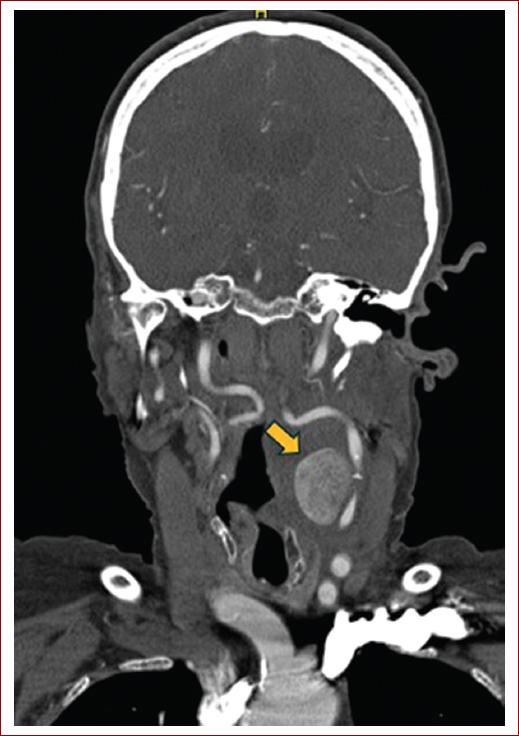

Ante un síndrome de Horner izquierdo con una masa cervical pulsátil, se sospechó de patología carotídea como primera alternativa diagnóstica. Con estos datos, se solicitó una angio-TC donde se observaba una masa hipercaptante a nivel de la bifurcación carotídea izquierda de 32 x 21 milímetros. Esta masa comprimía y desplazaba las estructuras vasculares lateralmente (Figs. 1 y 2).

Figura 1 Corte coronal de angiografía computarizada donde se observa masa hipercaptante en eje carotídeo izquierdo (flecha amarilla).